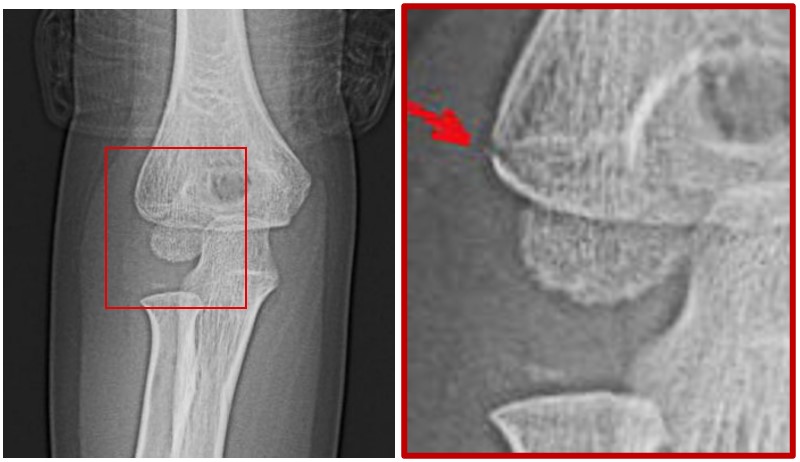

6才の男児ですが、保育園で転倒し右肘を打撲して、翌日右腕を動かさないということで受診した患者さんです。肘の腫脹は多少あるかなという程度でしたが、打撲という受傷原因があるので、肘内障でない可能性が高いと考えます。レントゲン撮影を行いました。

6才男 Xp1.jpg

図の赤矢印に軽微な異常があると疑いました。